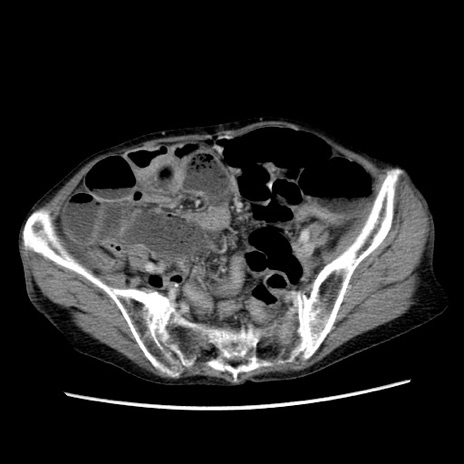

症例25(横断像)

【症例】80歳代女性

【主訴】胸のつかえ感

【現病歴】約9時間前に食後から胸のつかえた感じあり、嘔吐あり、来院。

【既往歴】胃癌(全摘)、胆摘、虫垂炎

【身体所見】心窩部に圧痛あり、反跳痛なし。

【データ】WBC 5700、CRP 0.05